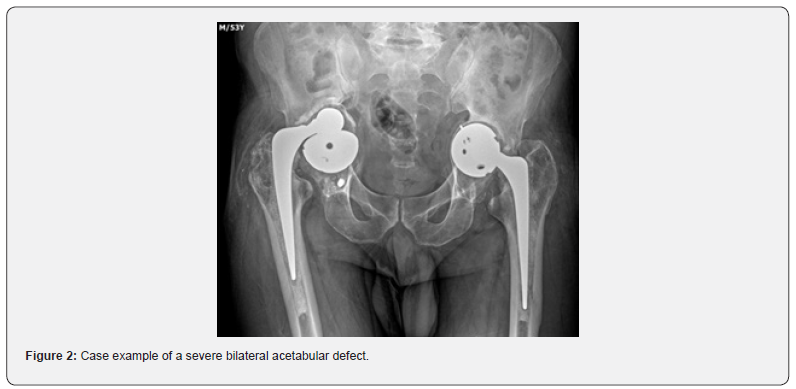

Regarding of bone defects, according to Paprosky classification [13] we have found a more severe proportion of lesions on the acetabular side: types 2B, 2C and 3A (case example figure 2) in decreasing order of frequency, while in the femoral side types 1 and 2 were more prevalent. Similar incidence was previously reported by Guimaraes et al [25], which demonstrated a prevalence in decreasing scale of acetabular defect types 3A, 2A and 2B. Extended time on a waiting queue for revision hip arthroplasty is often correlated with worsening acetabular defects, as prolonged delays can lead to increased bone loss and joint degeneration, complicating the surgical intervention and potentially compromising the long-term outcomes [26].